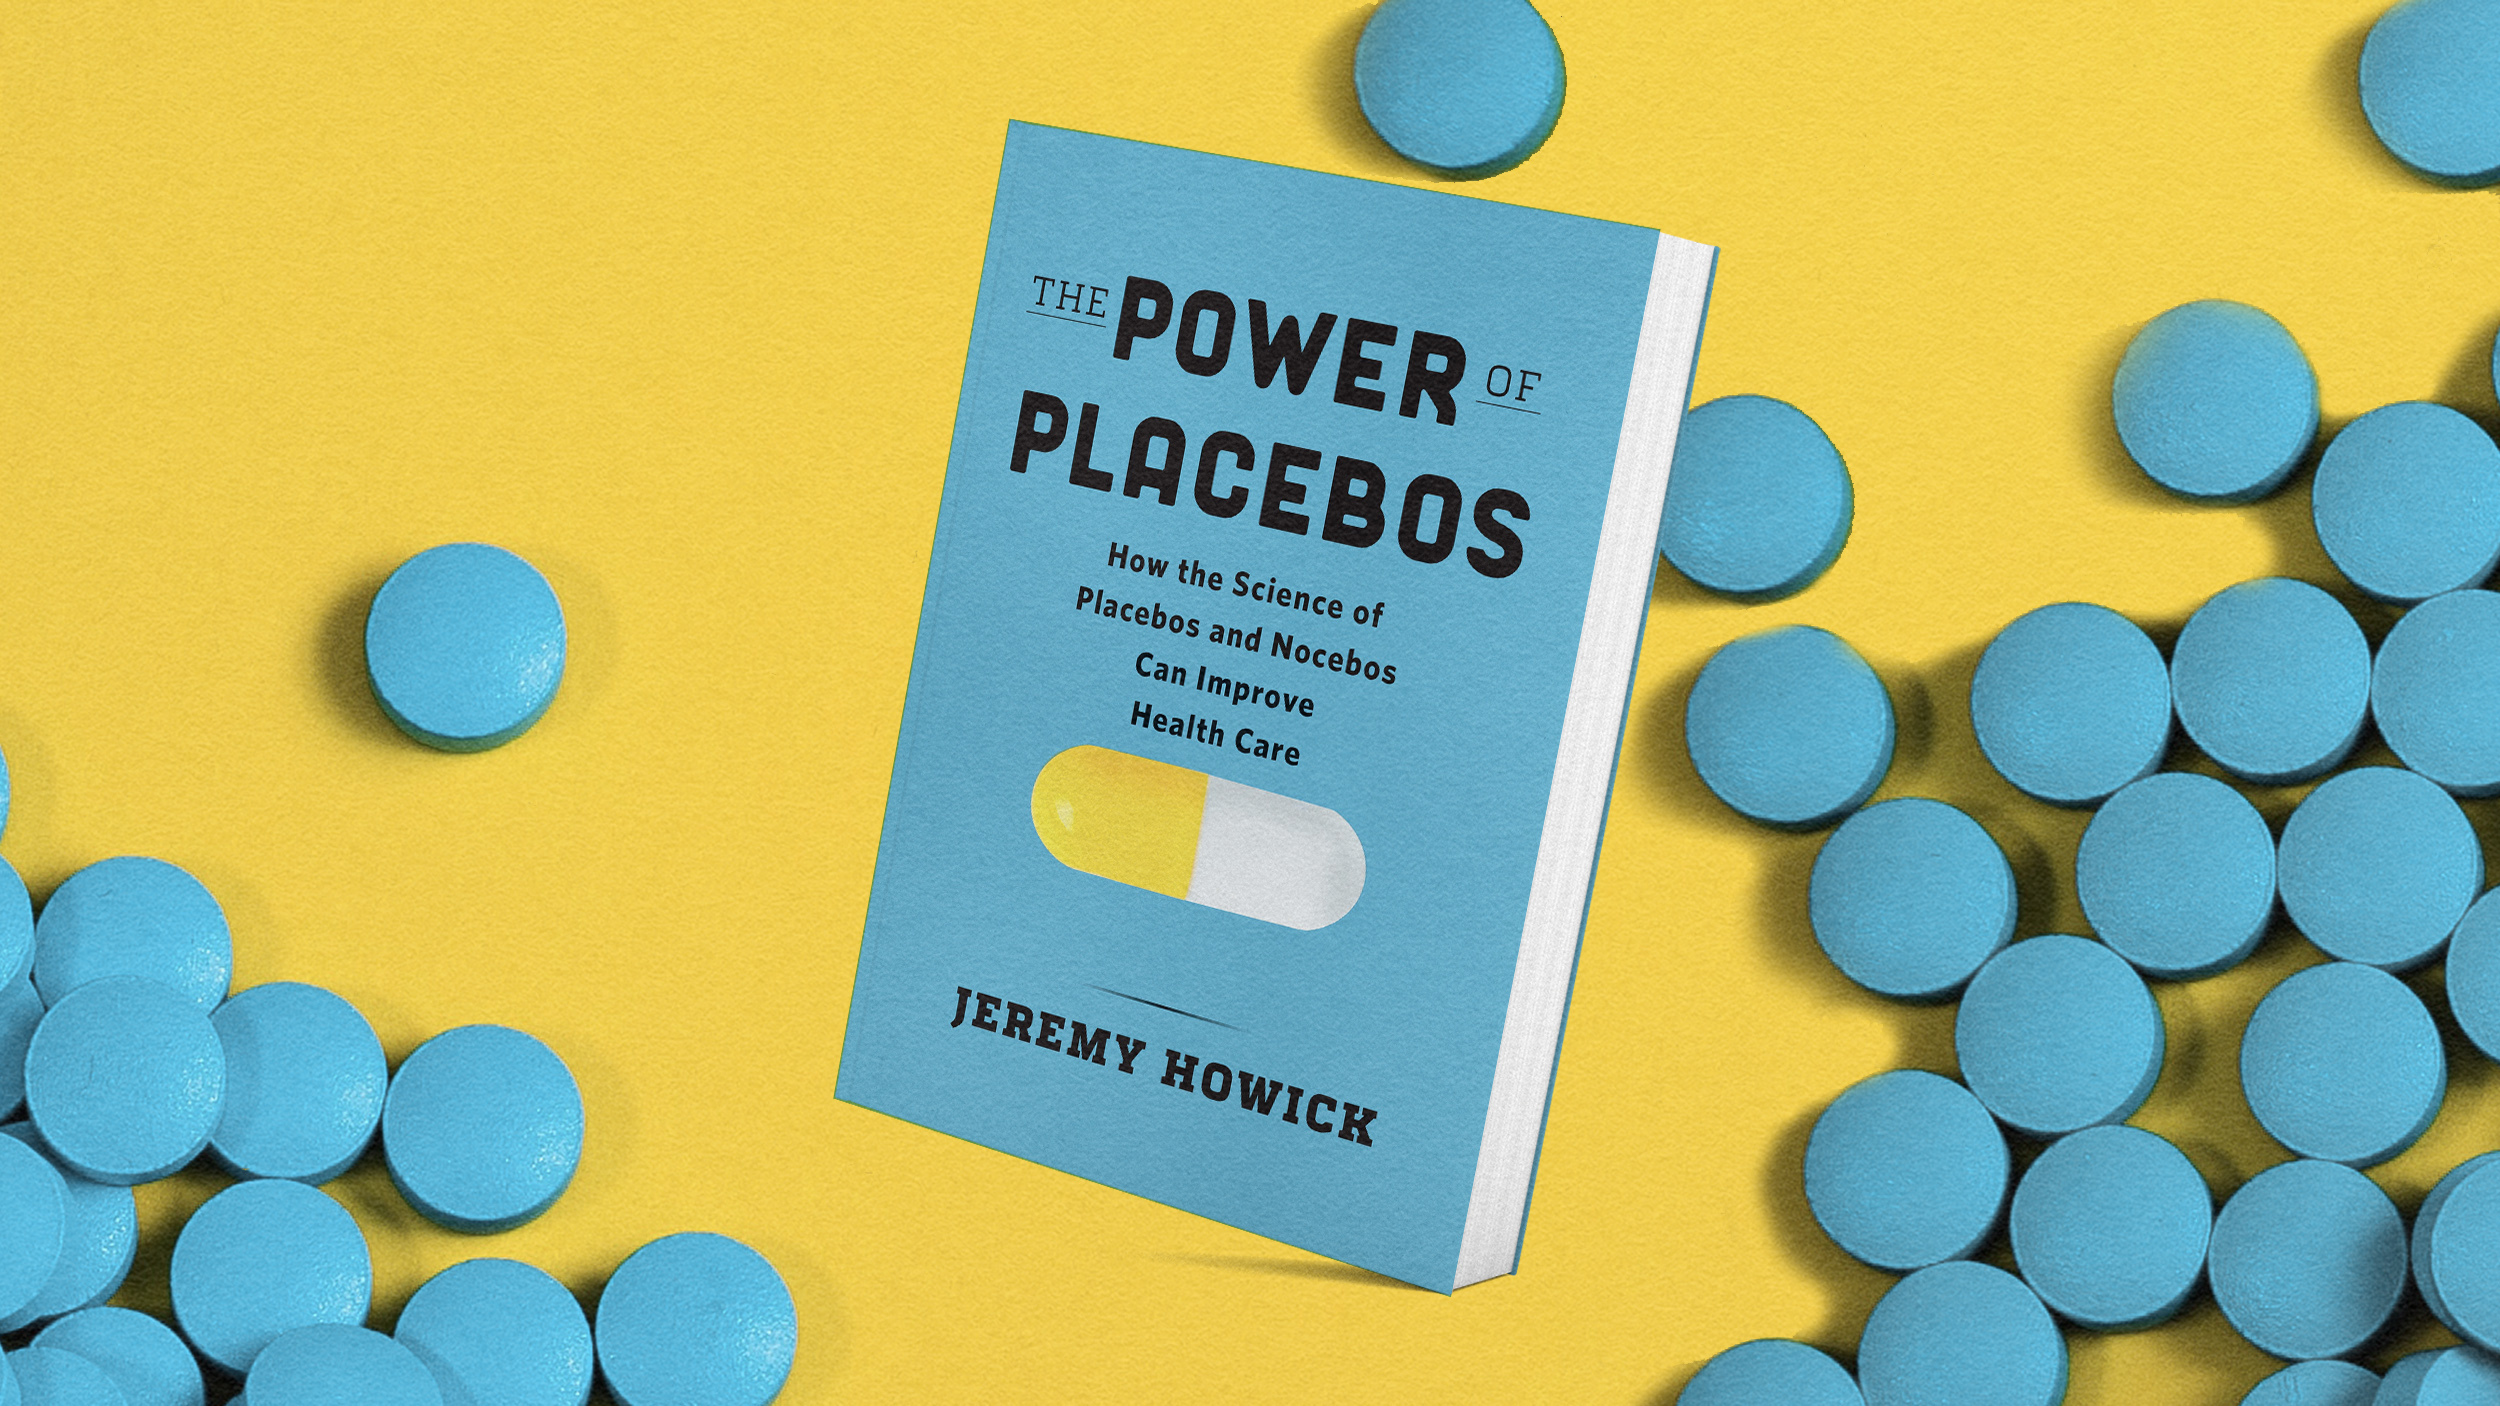

Placebo treatments don’t always need to be given deceptively to have positive effects.